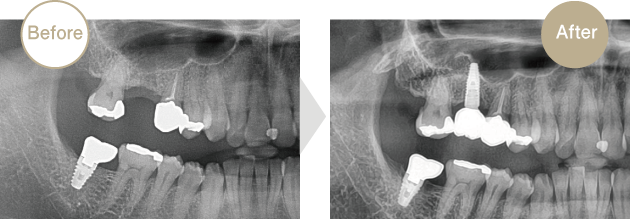

症例.02

上顎大臼歯部に骨が少ないため、上顎洞の骨造成を行いインプラントを埋入しました。